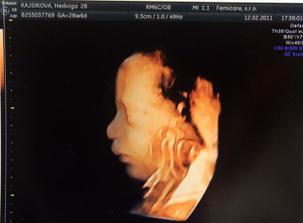

12.02.2011 dnes bol super deň, po dlhej dobe sme videli malého,mala som masáž bruška :D nožičky mal až pri hlavičke čo vystrájal netuším, aj sa mu štikútalo,len ja som nič necítila :°( ale super správička drobček je otočený hlavičkou dole,28+6tt máme 1197g a všetko vyzerá v poriadku :°) aj fotos nám pán dr. dal :°)